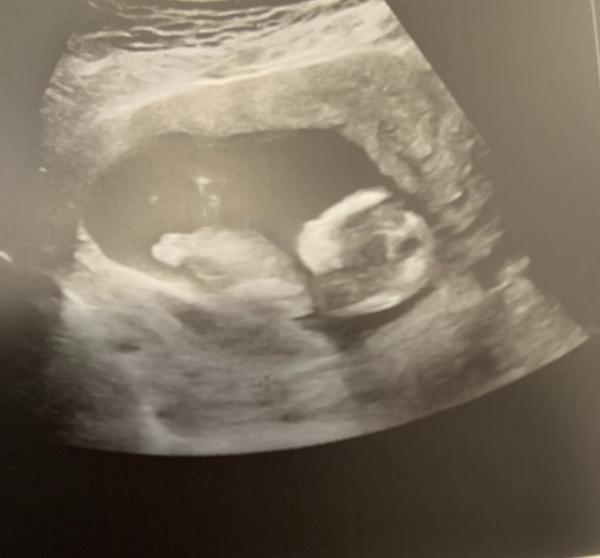

Guten Morgen ihr Lieben ich komme auch gerade von der Ärztin und meine Ängste sind endlich wieder weg. Babymaus hat sich fleißig bewegt und gewunken. Soooo sĂŒĂŸ muss nur nĂ€chste Woche zum Zuckertest, da ich wieder Zucker im Urin hatte und sie von einer SS Diabetes ausgeht. Habe etwas mehr Fruchtwasser wie es sein soll. Hatte ja schon mal eine und bin kein Federgewicht und daher wohl dafĂŒr gefĂ€hrdet. Naja wenn ansonsten mit meinem WĂŒrmchen alles gut ist, ist alles super Ist schön gewachsen, nun 7,3 cm SSL und laut GerĂ€t insgesamt 12 cm groß. Weiß aber nicht ob das nun mit der Fruchtblase gemessen wurde oder den Beinchen. Hatte ja Angst das es zu klein ist. Als ich nach dem Geschlecht fragte sagte sie, dass sie das erst in der 20. Woche schaut und mich gedulden muss naja nicht schlimm. Einen „Zippel“ habe ich nun nicht gesehen und mein Mann auch nicht aber wir warten mal ab das MĂ€uschen hat schön zwischendurch die Beinchen an die Decke gestemmt und paar Mal gewunken. Das war genial allen einen schönen Tag und bin gespannt auf eure Berichte. Liebe GrĂŒĂŸe

Ach hier noch ein schönes Profilbild von der Seite. Sie wollte das NÀschen besser sehen